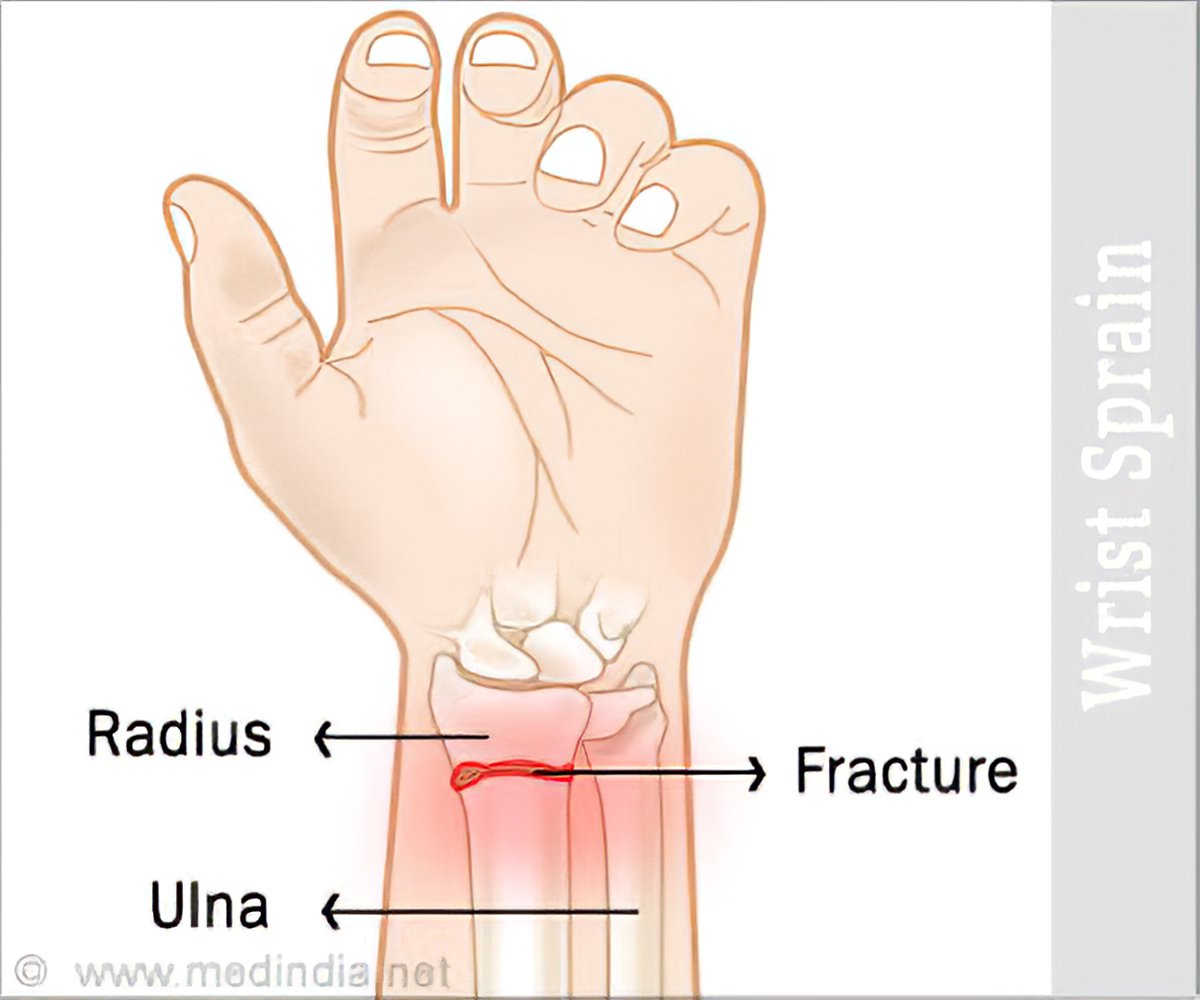

Wrist Sprain – Causes, Symptoms, Diagnosis, Treatment

Sprained Wrist Symptoms | Florida Orthopaedic Institute

Wrist Dislocation|Types|Causes|Signs|Symptoms|Treatment|Exercises …

Sprain or fracture? You need to know | Healthy Headlines

sprained wrist – Google Search | Sprained wrist, Wrist anatomy, Bone …